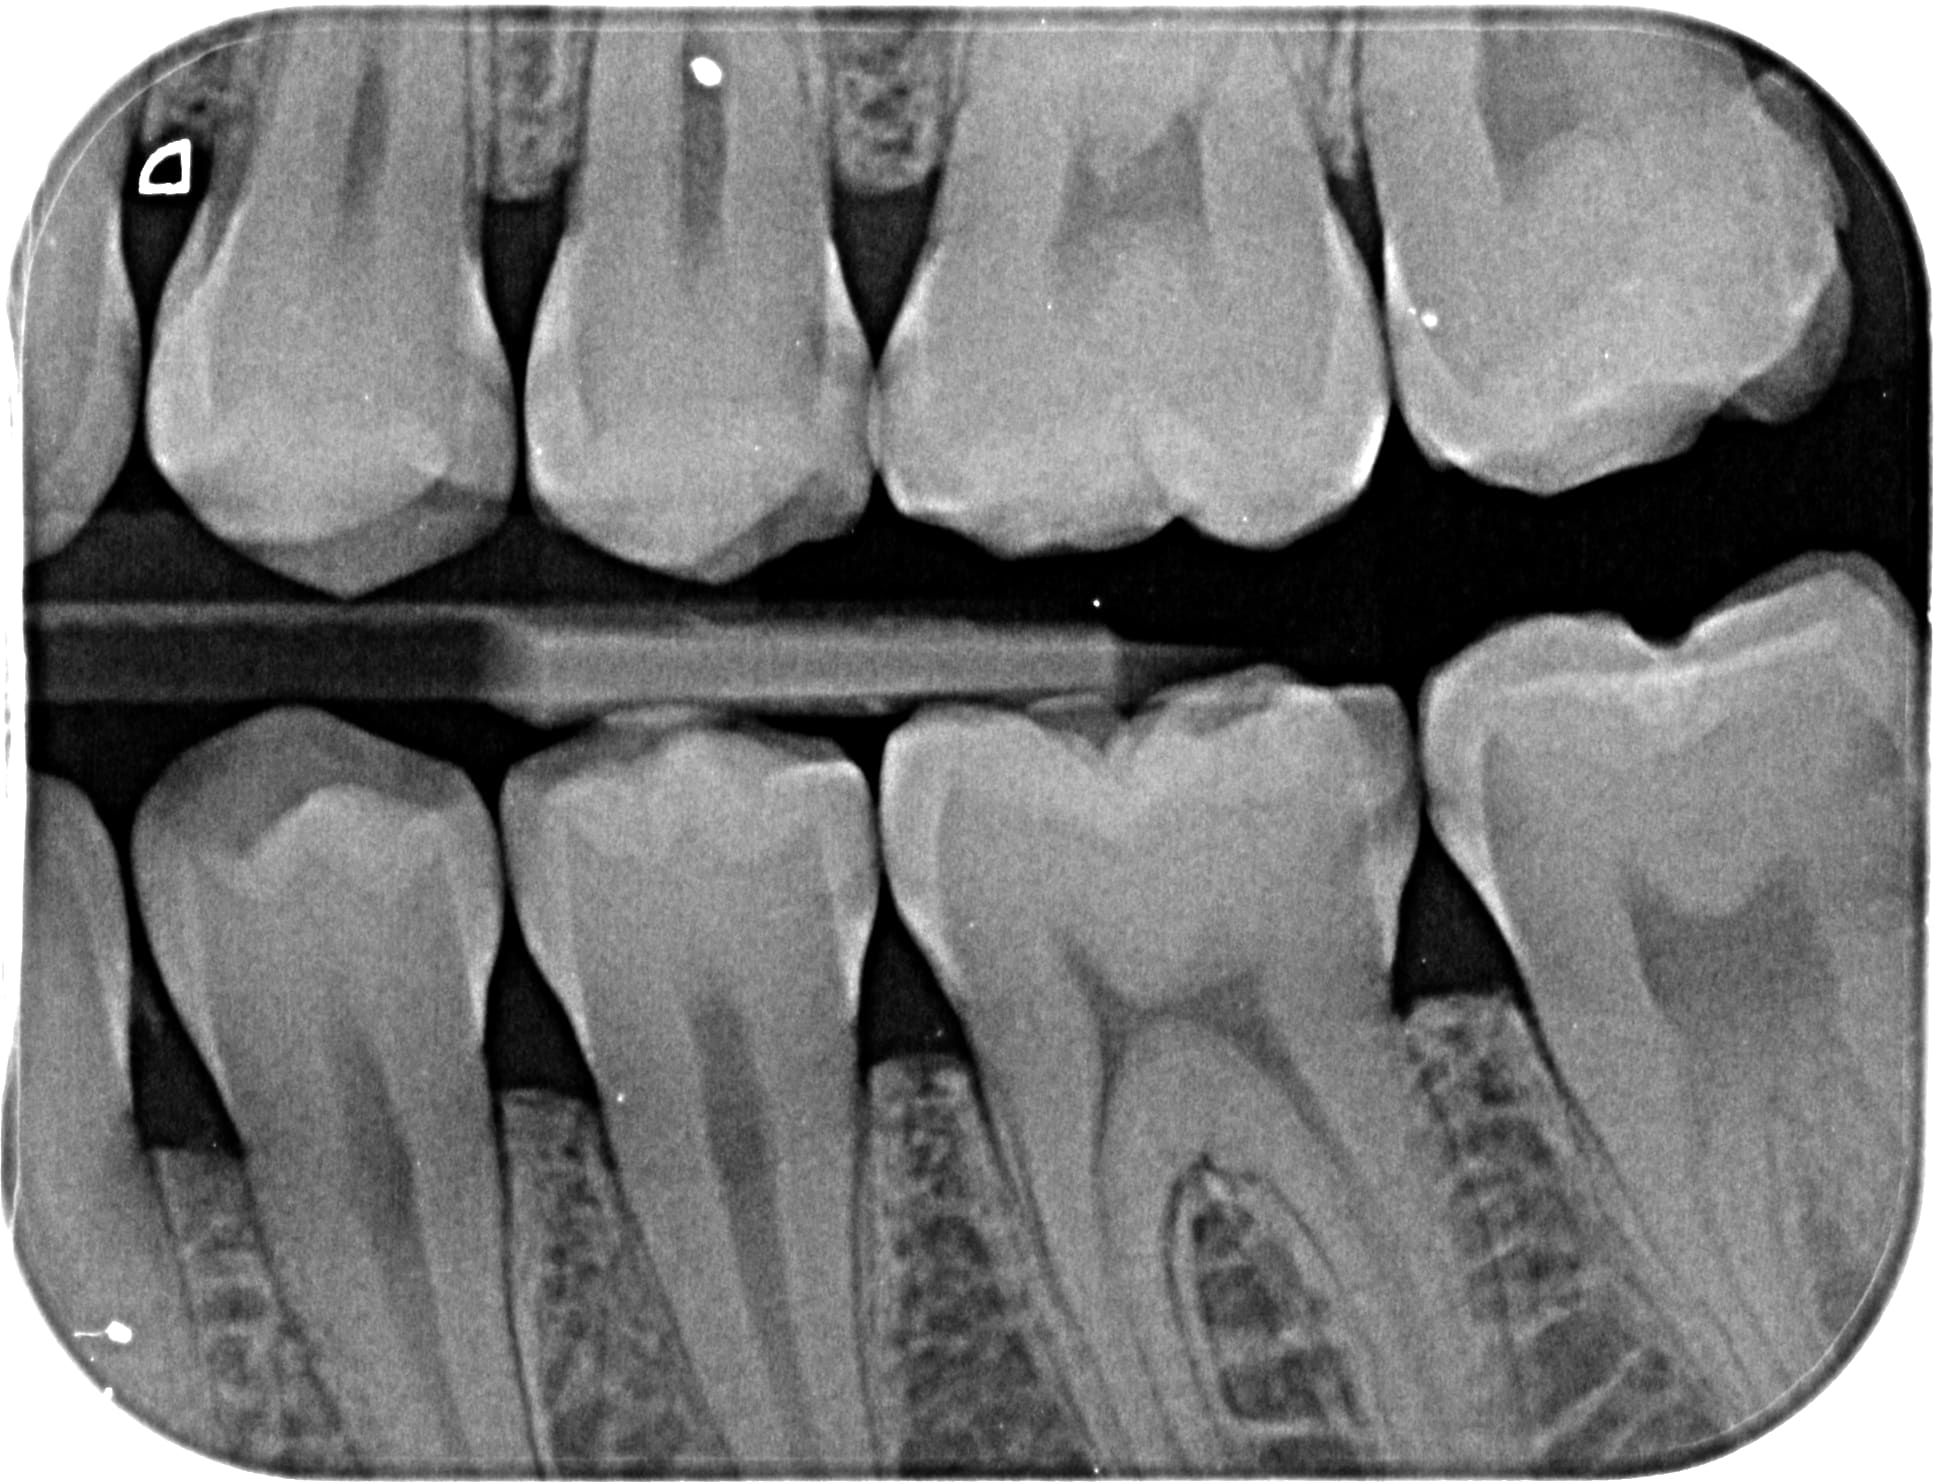

Sinon a ton avis je vais prendre combien de temps et dégager combien de BNC sur ce jeune patient de 18 ans (2bw) ? Est-ce qu'une cam a 8600e/an + 2000e/an de logiciel va m'aider ?? (60% du temps d'un omni... attention y'a un piège... ;)

Combien m'a coutée l'empreinte impregum pour le petit bridge sur implant et combien de temps de rdv ?? Sans cam a 43ke ?